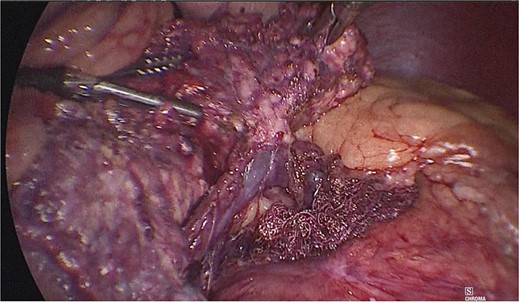

Once the above procedure was completed, it was dissected along the neck of the pancreas to identify the superior mesenteric vein and splenic vein. An incision was made along the superior border of the pancreas, to the left of the gastroduodenal artery and inferior to the hepatic artery. A plane was created between the portal vein and neck of the pancreas by blunt dissection from the inferior to the superior direction with a blunt-tipped laparoscopic dissector (Fig. 2).

A plane was created between the portal vein and the neck of the pancreas by blunt dissection.